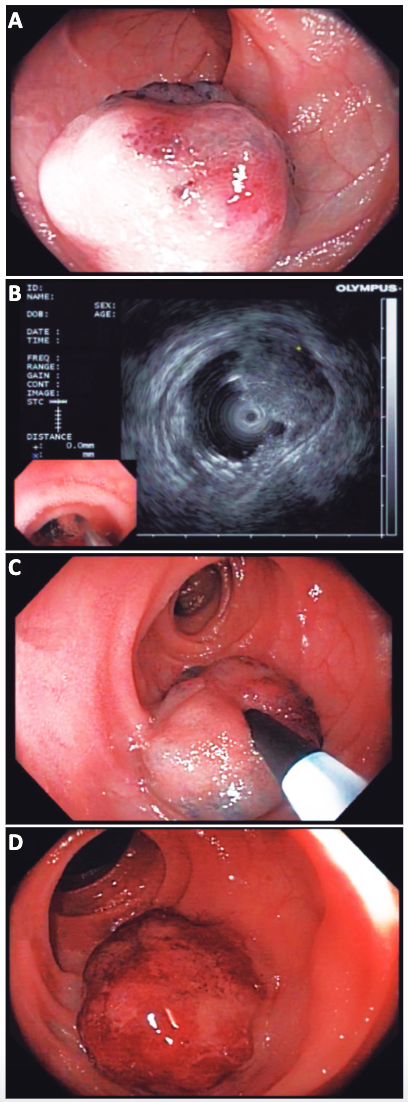

Se evaluó dicha lesión con ultrasonografía endoscópica con minisonda radial de 12 Hertz, y se observó lesión hipoecoica localizada en la capa submucosa, que podría corresponder a hemangioma. Se decidió realizar tratamiento endoscópico con escleroterapia con polidocanol al 1%. Se posicionó la lesión en hora 6, y se inyectaron con aguja de 21 gauges ocho mililitros de solución de polidocanol al 1%, evidenciándose cambio de coloración y aumento del tamaño de la lesión (Figura 1). El paciente no presentó complicaciones posteriores al tratamiento (Vídeo 2), y evolucionó favorablemente, con mejoría de los parámetros hematimétricos, sin necesidad de transfusiones ni requerimientos de hierro endovenoso.

Figura 1. Imágenes endoscópicas de hemangioma de intestino delgado.

A. Lesión elevada lobulada azulada, de 30 mm de diámetro. B.

Ultrasonografía endoscópica con mini sonda radial de 12 Hertz, donde se evidencia lesión hipoecoica de 30 mm

localizada en la capa mucosa del intestino delgado, compatible con hemangioma. C. Inyección de polidocanol

al 1% con aguja de 21 gauges. D. Cambio de tamaño y de coloración posterior a la inyección.